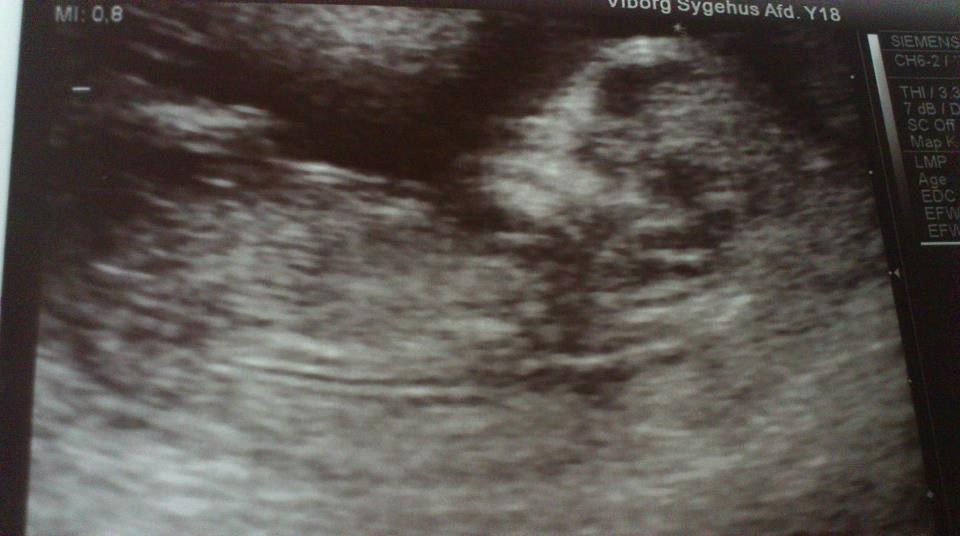

Min lille baby havde det fantastisk

De gav mig ikke tallene, men sagde at jeg lå i den lave ende mht risiko

Var lige ved at tude da jeg hørte hjertet

Det er altså virkelig bare så fint et billede det der